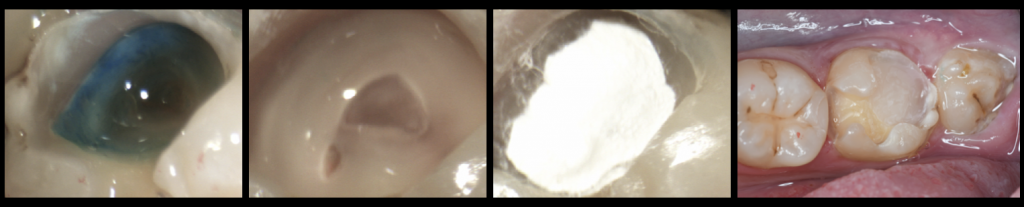

写真左・中左・中右:う蝕検知液をもちい虫歯:う蝕を除去除去していくと歯の神経(歯髄)まで到達。ダイヤモンドチップにて歯の神経(歯髄)を切断。切断面の確認。生理食塩水にて止血後、MTAにて直接覆髄。メガボンド2(クラレノリタケデンタル)をもちいてコンポジットレジンにて封鎖。

写真右:封鎖後、形成を行い、セレックプライムスキャンを用いて光学印象を行い、

セラミック修復物の製作(VITA MarkⅡ 2M1C)